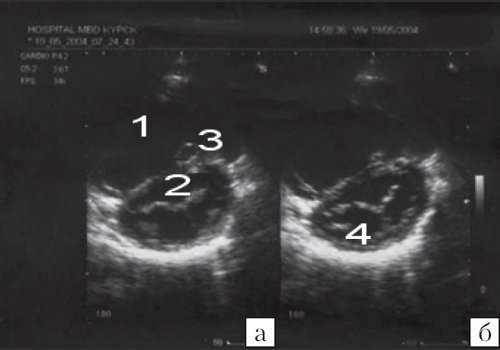

![Эхокардиограмма больного C (а - парастернальная позиция по длинной оси, б - парастернальная позиция по короткой оси на уровне аорты)]()

Рис. 4. Эхокардиограмма больного С.

а) - парастернальная позиция по длинной оси;

б) - парастернальная позиция по короткой оси на уровне аорты.1 - правый желудочек; 2 - аорта; 3 - левое предсердие; 4 - левый желудочек; 5 - дефект межжелудочковой перегородки; 6 - аневризма межжелудочковой перегородки; 7 - правое предсердие.